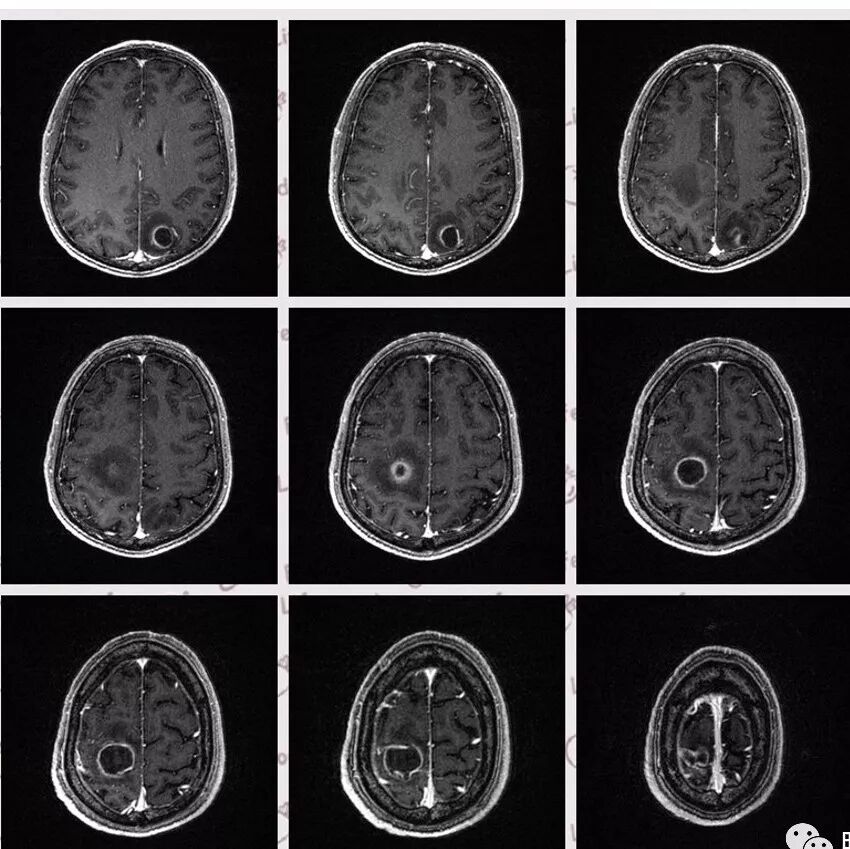

右肺下叶团块状密度增高影,边缘模糊,其内见液性低密度影,多发小气泡影及充气支气管征,考虑肺脓肿。颅内双侧顶叶长T2长T2病灶,周围水肿,DWI高信号,增强扫描囊壁环形强化,囊壁钙化,周围水肿,考虑脑脓肿。患者长期接触垃圾,什么菌都有,肺、脑脓肿,考虑肺克。再有肝脓肿就更支持了。

右肺下叶背段实变,广基底,糊墙,长轴与平行胸膜,周围有晕,支气管进入堵塞,可见低密度坏死及小空泡。颅内多发环形强化灶,符合脑脓肿三层结构,结合临床,考虑:感染性病变,隐球菌?鉴别肺克。

颅内多发类圆形等或长T1长T2信号,周围见少量环形水肿带,考虑多发脓肿,不符合转移瘤表现。综合肺脑脓肿,考虑隐球菌可能

右肺下叶见不规则软组织影,边缘不清,内夹杂气体,背段支气管未见明显阻断,增强扫描下叶病灶内见类圆形低强化区,其边缘光滑,见低强化区壁,颅脑左侧枕叶及双侧顶叶见多发长T1长T2信号,T2高信号内见类圆形异常信号,壁呈低信号,DWI环形壁未弥散受限,内容物弥散受限,周围为水肿区,增强扫描呈多发环形强化,考虑血源型感染,颅内及右肺下叶脓肿形成

DWI值对鉴别脑脓肿与囊性脑转移瘤有重要意义。包膜期脑脓肿其内容物主要为炎症细胞、微生物及蛋白质,其黏稠度相对较高,水分子弥散受到限制,DWI表现为均匀高信号。转移瘤囊变区主要以浆液性坏死物为主,其黏稠度相对较低,水分子扩散速度相对较快,DWI表现为低信号

脑脓肿和囊性脑转移瘤的鉴别点就是粘液(结合水)浆液(自由水)的鉴别

下图是例举其他病例:

颅内环形的高信号,但是可以发现这个的DWI环是厚的,但是增强扫描的环是非常薄的,如果是肿瘤的,就是壁的弥散受限是肿瘤细胞的话,那么他强化的环应该跟DWI的环的厚度是一样的,所以这个环形的低DWI高信号应该是脓肿。而且就是关于这个脓腔壁的,就是脓腔的外壁是非常模糊的,而内壁还是相对光整,环不是很完整。下面一个图,没有给到,DWI上可以看到沿着破溃的脓肿壁向外侵出去的感觉,如果是环形转移的,那么它的那个内壁是更加不光整,而外壁是相对比较清楚一些的。

这个颅内病灶增强扫描的无强化区范围与DWI高信号范围是一致的,所以还是脓腔内受限,至少时期不那么典型,不是纯粹的高信号,DWI是厚层、增强是薄层;而且扫描角度也不一样,所以无法完全对上

脓肿内的坏死、脓液形成也不是一次性完全形成的,就像在肝脓肿内,信号也是不一致的。重点还是在于强化区的地方弥散受限了还是无强化区的地方受限了,还是那句话,强化壁比弥散壁薄很多,无强化区比弥散不受限区范围大多了

3.脑内多发混杂信号病灶,显著长T1、显著长T2信号为主。注意TW1及TW2均显示环形等密度影(这在转移瘤是非常罕见的)且出现相应的环形强化。中央液化区DW扩散受限以及周边广泛水肿等,都符合典型多发脑脓肿改变。

4.脓腔较大,也更符合细菌感染。(脑内结核、隐球菌及奴卡菌感染病灶通常不易有如此大范围)

综上患者符合肺脓肿及脑脓肿诊断,病原菌以肺炎克雷伯杆菌等感染可能性较大